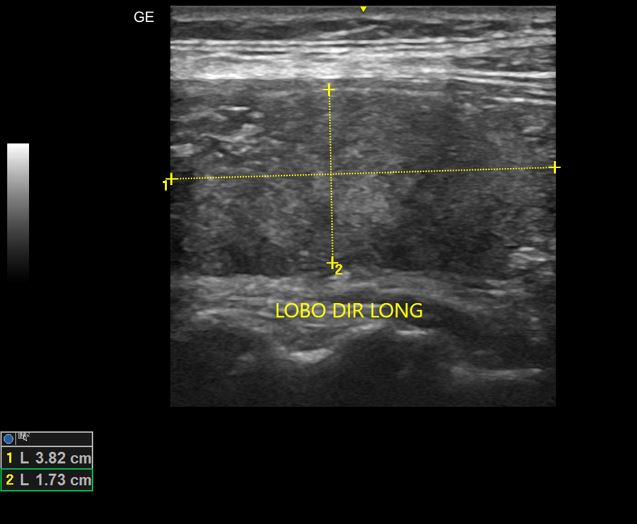

Nódulos de Tireoide

USG de nódulos benignos